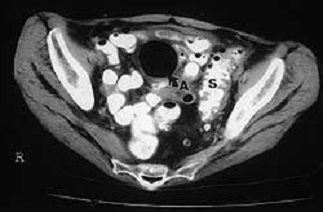

Рис. 4 Компьютерная

томография с контрастированием: дивертикулярная болезнь сигмовидной кишки (S),

осложнившаяся с образованием абсцесса (А), содержащего большое количество газа

(стрелка).

КТ с контрастным усилением -

это исследование выбора у больных с острым дивертикулитом. Часто при ее

проведении обнаруживается характерное утолщение стенок толстой кишки с

воспалением окружающей ее жировой клетчатки. В осложненных случаях при КТ

выявляются абсцессы, газ

и/или контрастное вещество вне петель кишки. Во многих отделениях практикуется

дренирование абсцессов в брюшной полости под контролем КТ, что помогает

обойтись без оперативных вмешательств в острую фазу заболевания.